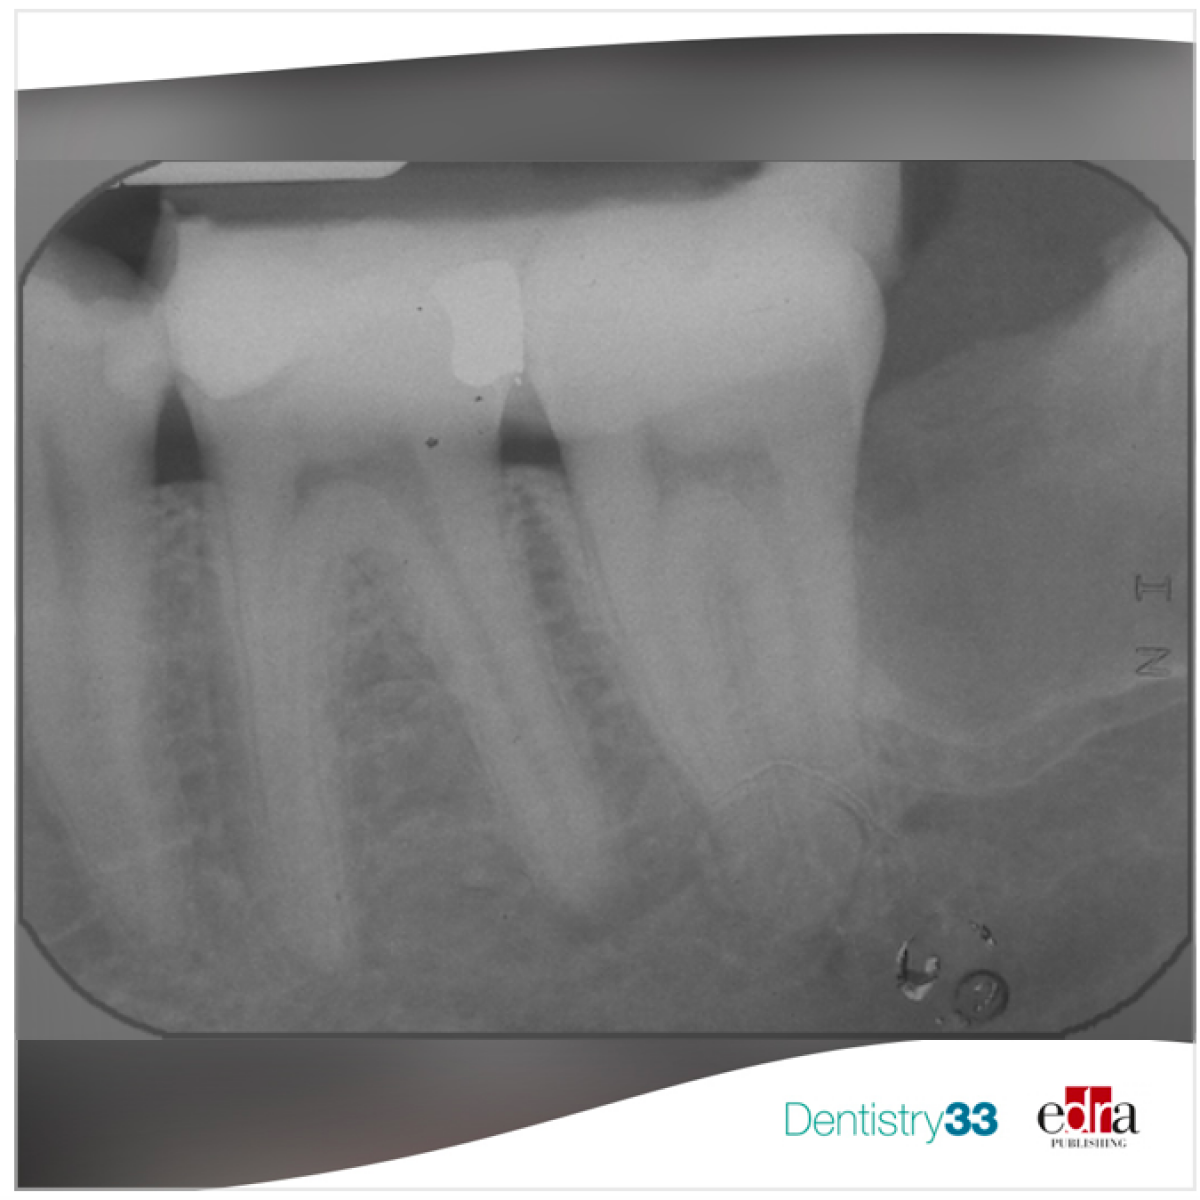

This ambispective cohort study included patients who received primary/secondary root canal therapy from 1986 to 1998 performed by a single operator in a private practice. Outcomes measures were: tooth survival; clinical and radiographic success, as assessed by the treating clinician and an independent outcome assessor; and complications, as evaluated 20 years after treatment. Descriptive statistics, life table and Cox regression analyses for survival were fitted.

Four hundred and eleven patients (59% affected by advanced periodontitis) with 1169 endodontically treated teeth were identified (703 treatment, 466 retreatment). Drop-outs at 20-year follow-up were 128 patients (31.1%) with 388 (33.2%) teeth. Forty teeth (3.4%) in 30 patients experienced endodontic complications, subsequently successfully treated. Clinical and radiographic evaluation revealed: complete clinical success in 542 teeth (69.7%), partial success in 10 (1.3%), partial failure in 75 (9.6%), and failure in 151 (19.4%) (10 extracted for endodontic reasons, 58 due to periodontitis, and 58 vertical fracture). Life table analysis revealed 86% tooth survival at 20-year follow-up. The chance of survival decreased with increasing patient age (P = 0.006). Re-treated teeth had better survival than treated teeth (P = 0.024) Canines and premolars had better chances of survival than incisors (P = 0.002 and P = 0.015, respectively). Teeth treated at two sittings (with intermediate medication) had reduced chances of survival as compared to teeth treated at one sitting (P = 0.027). Teeth treated for the first time for endodontic reasons exhibited a better chance of survival than teeth treated for periodontal and prosthetic reasons (P = 0.012).

The 20-year prognosis of endodontically treated/re-treated teeth as part of multidisciplinary rehabilitation of patients affected by advanced periodontitis is good. Aging, two-stage endodontic treatment, and endodontic treatment for non-endodontic reasons are important predictors of failure.